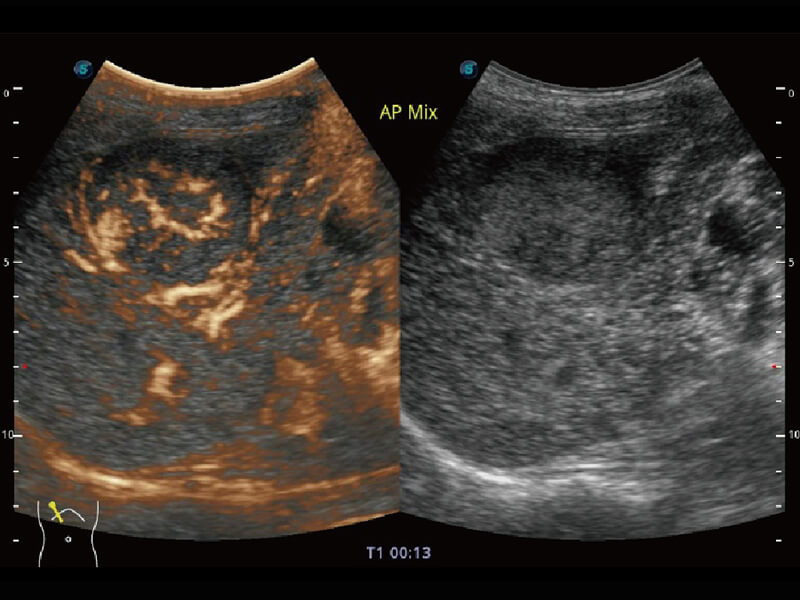

性能优异的硬件架构,极大提升超声系统的运行效率和数据处理能力。相比以往超声成像系统,Wis+平台为您带来极快的响应速度和成像帧频,提升检查流畅度。

S60探头工艺,从前端信号处理每一个环节采集无损声学数据,真实还原组织原貌,再现解剖细节。